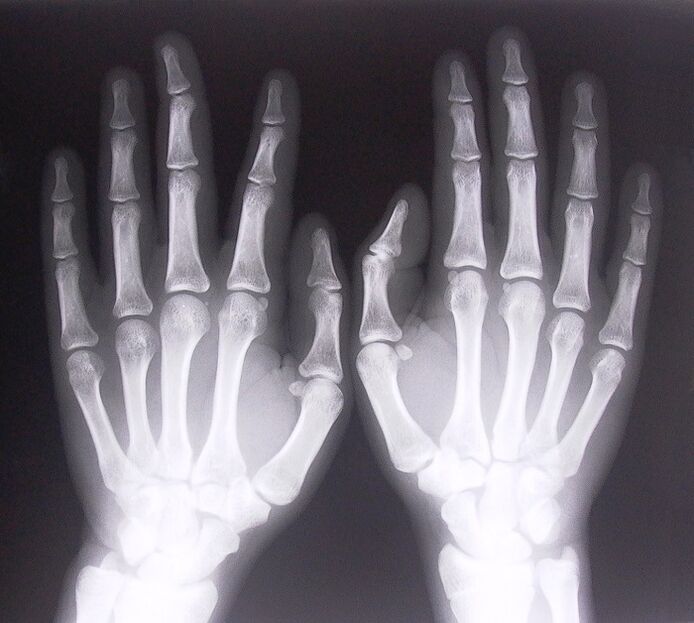

- Zwężające się zapalenie więzadeł. Aby zidentyfikować przyczynę choroby, konieczne jest poddanie się prześwietleniu rentgenowskiemu. Objawy są typowe: bolesne ruchy ręki, zapętlenie zaciśniętej dłoni. Ponadto podczas przedłużania zwykle słychać kliknięcia.

Aby rozpocząć leczenie bólu stawów w palcach, musisz poprawnie określić, jaka choroba je spowodowała. Aby ustalić, na jaką chorobę cierpi osoba odczuwająca ból stawów podczas zginania ramion, lekarze zalecają wykonanie następujących zabiegów:

- Zrób zdjęcia rentgenowskie.